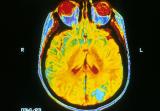

Австралийские ученые из Университета Квинсленда значительно продвинулись в лечении травм головного мозга. Они нашли иммунные клетки, которые поддерживают процесс регенерации, пишет Xinhua. Эксперты фокусировались...